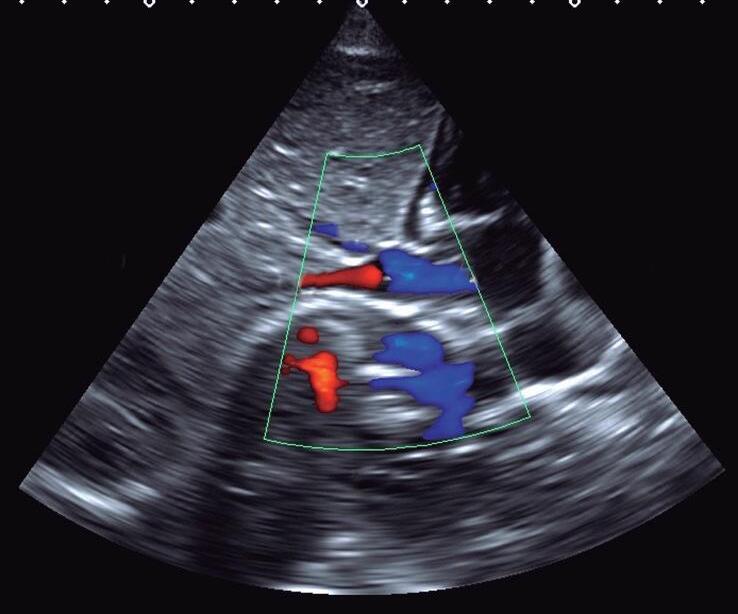

Para obter o plano paraesternal eixo curto, “rodamos” o transdutor no sentido horário com o index apontando para o ombro esquerdo do paciente (▶ Vídeos 1-17 e 1-18). A visão eixo curto das grandes artérias consiste em valva aórtica (posicionada no centro da imagem), via de saída do VD (região infundibulovalvar do VD e artéria pulmonar), valva tricúspide e átrios (Fig. 1-7a e ▶ Vídeo 1-19). Movimentando o transdutor no sentido craniocaudal também é possível obtermos o eixo curto dos ventrículos ao nível dos músculos papilares e da valva mitral para a análise da contratilidade ventricular, do septo interventricular muscular e da valva mitral (Figs. 1-5b e 1-7b, c; ▶ Vídeos 1-17, 1-18, 1-20 e 1-21). O mapeamento em cores é importante para pesquisa de comunicação interventricular muscular e disfunção valvar mitral (Fig. 1-7).

Fig. 1-7. Plano paraesternal eixo curto com Doppler colorido: grandes artérias (a), eixo curto dos ventrículos ao nível dos músculos papilares (b) e da valva mitral (c). AD: átrio direito; AE: átrio esquerdo; VD: ventrículo direito; Ao: aorta; AP: artéria pulmonar; VT; valva tricúspide; VP: valva pulmonar; VE: ventrículo esquerdo; S: septo interventricular; mp: músculo papilar; VM: valva mitral.